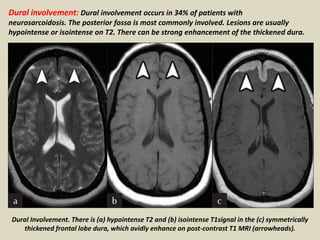

Dural involvement: Dural involvement occurs in 34% of patients with

neurosarcoidosis. The posterior fossa is most commonly involved. Lesions are usually

hypointense or isointense on T2. There can be strong enhancement of the thickened dura.

Dural Involvement. There is (a) hypointense T2 and (b) isointense T1signal in the (c) symmetrically

thickened frontal lobe dura, which avidly enhance on post-contrast T1 MRI (arrowheads).